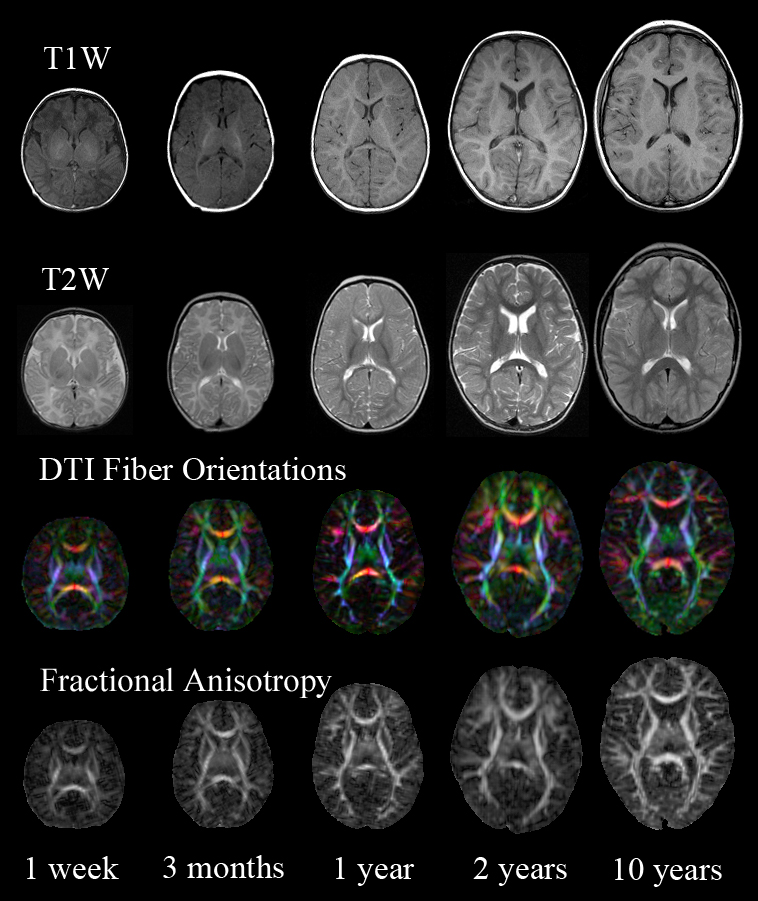

• 8 year study

• Longitudinal data

• 532 subjects

• 8000 distinct variables

• 37000 individual assessments

• T1, T2, PD, DTI

• Spectroscopy

• ∼3TB of imaging data

• 2000 MRI acquisitions

• Infant brain development in autism

• 3000+ scans

• 700+ subjects

• 7000 distinct variables

• 150,000+ individual assessments

• T1, T2, DTI, BOLD

• ∼5 TBs of imaging data

• Genetic/biospecimen data